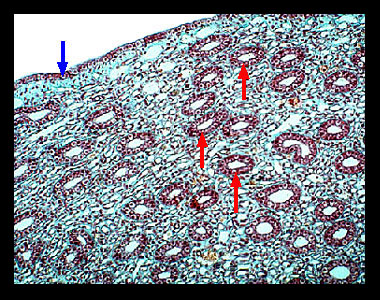

Solved Label the photomicrogram of the trachea. Cilia Lamina - Chegg Label the photomicrogram of the trachea. Cilia Lamina propria Submucosa Cilia Basement membrane Submucosa Epithelium Basement membrane Lamina propria Epithellum This problem has been solved! You'll get a detailed solution from a subject matter expert that helps you learn core concepts. See Answer Question: Label the photomicrogram of the trachea. Lab 2: Microscopy and the Study of Tissues - UW-La Crosse This slide showing a cross section of the mammalian trachea (wind pipe) contains examples of several different kinds of tissues. In addition to the pseudostratified columnar epithelium lining the trachea and hyaline cartilage, also seen on this slide is an extensive area of adipose tissue, which is specialized for fat storage. Label the photomicrogram of the trachea. - Brainly.com The trachea is known to be a kind of long tube that links the human larynx (voice box) to that of their bronchi. Note that the bronchi is one that send air to a person's lungs and the trachea is known to be an essential part of man's respiratory system. Hence, The Label of the photomicrogram of the trachea is given in the image attached.

Anatomy, Head and Neck, Trachea - StatPearls - NCBI Bookshelf The trachea is a U-shaped structure that is composed of hyaline cartilage on the anterior and lateral walls, with the trachealis smooth muscle forming the posterior border of the trachea. The entire tracheal lumen is lined by ciliated pseudostratified columnar and goblet cells that create the tracheal mucosa. The trachea is part of the conducting airway system that begins immediately inferior ... Bronchus and branchial wall: anatomy and diagram | GetBodySmart Bronchus and bronchial wall: anatomy and function. The bronchi are part of the airway system of the lower respiratory system. Bronchi are the branches of the trachea which provide oxygen to the lungs. In cross-section, the bronchial wall appears similar to the trachea. Respiratory mucosa (or mucous membrane) lines the luminal surface. photomicrograph of the tracheal wall (p119.1-2).docx - In... photomicrograph of the tracheal wall (p119.1-2).docx 639C1EA0-A029-4921-815C-2114F8116F4F.jpeg d When you work out your muscles use up more oxygen than usual so your blood document Screen Shot 2023-01-27 at 8.24.51 PM.png Show More Trachea: Anatomy, blood supply, innervation and function - Kenhub The trachea is a D-shaped fibrocartilaginous respiratory organ. It consists of 16-20 tracheal cartilages anterolaterally and a fibromuscular wall posteriorly. The tracheal cartilages are composed of hyaline cartilage and interconnected by fibroelastic tissue.

Lab 2: Microscopy and the Study of Tissues - UW-La Crosse This slide showing a cross section of the mammalian trachea (wind pipe) contains examples of several different kinds of tissues. In addition to the pseudostratified columnar epithelium lining the trachea and hyaline cartilage, also seen on this slide is an extensive area of adipose tissue, which is specialized for fat storage.